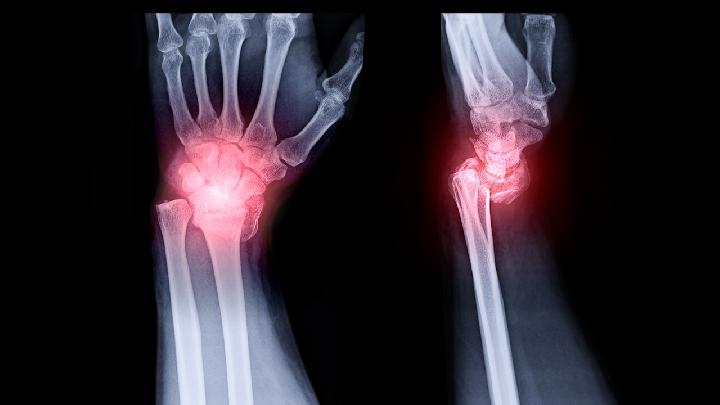

生活中骨质疏松患者如何保健?相信很多人都有这方面的疑问吧,良好有效的保健不仅可以预防骨质疏松疾病,还可以帮助护理尽早治愈骨质疏松疾病,防止骨质疏松的反复发作,有着非常大的作用。因此,我们需要了解一下骨质疏松的保健措施。

骨质疏松的日常护理要控制饮食结构,避免酸性物质摄入过量,加剧酸性体质。大多数的蔬菜水果都属于碱性食物,而大多数的肉类、谷物、糖、酒、鱼虾等类食物都属于酸性食物,健康人每天的酸性食物和碱性食物的摄入比例应遵守1:4的比例。壳寡肽为一种动物性活性碱,能迅速排除人体体液偏酸性物质,能维持血液中钙浓度的稳定,保持人体弱碱性环境是预防和缓解骨质疏松。

防止缺钙,养成良好的生活习惯。骨质疏松的日常护理中需要避免酸性物质摄入过量,加剧酸性体质。如彻夜打游戏、打麻将、夜不归宿等生活无规律,都会加重体质酸化。应当养成良好的生活习惯,从而保持弱碱性体质,预防骨质疏松症的发生。

多进行户外运动。进行户外运动以及接受适量的日光照射,都有利于钙的吸收。运动中肌肉收缩、直接作用于骨骼的牵拉,会有助于增加骨密度。因此,适当运动对预防骨质疏松亦是有益处的。